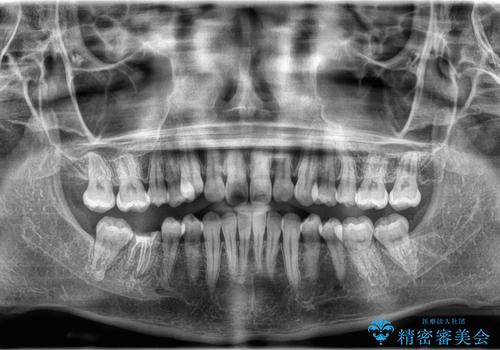

非抜歯矯正で八重歯を改善|短期間8か月で美しい歯並びに|インビザラインライト上顎のみで矯正

- 「八重歯を治したい」との主訴でご来院された患者様です。。

非抜歯で上顎のみインビザラインライトを使用して矯正を行いました。

短期間(約8か月)の治療で歯並びが整い、患者様も大変喜ばれました。